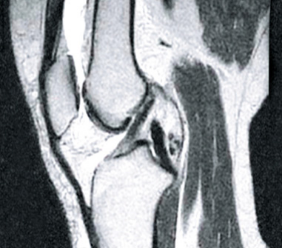

PRIJE

Na slici lijevo vidljivi su prazni prostori unutar zglobne čahure nastali zbog prekomjernog nakupljanja tekućine u tkivu. Nakon tretmana, struktura sinovijalne tekućine se obnovila (slika desno), povratila viskozno-elastičnu konzistenciju i svojstva podmazivanja. Kosti su pravilno "podmazane", zahvaljujući čemu se ne strugaju jedna o drugu, jer su obnovljene amortizacijske funkcije zgloba.